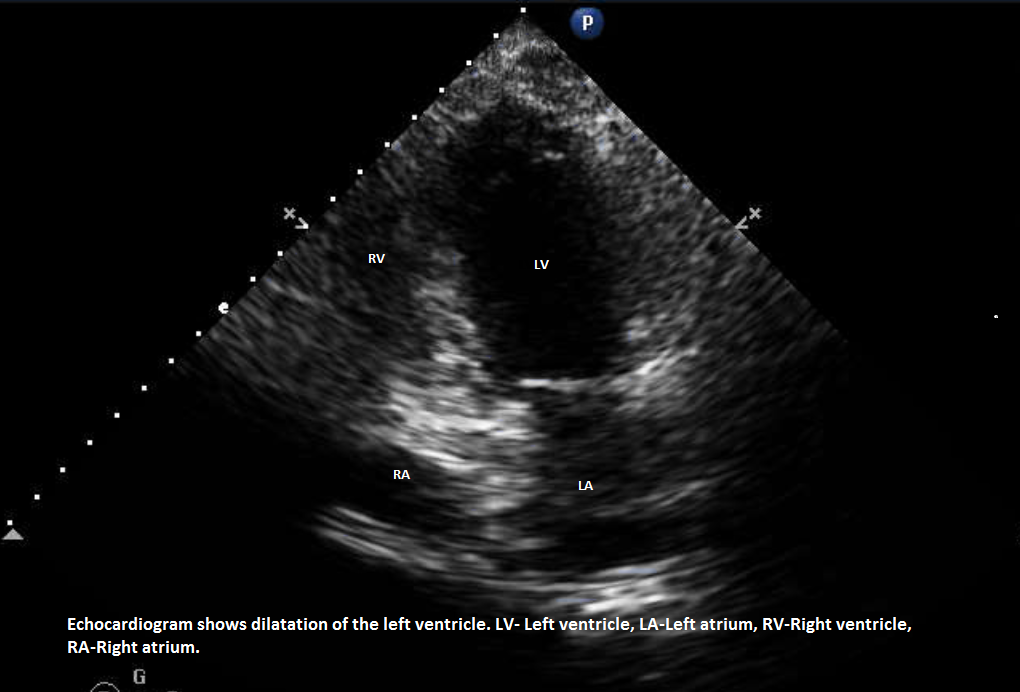

A 52-year-old Asian woman with end-stage liver disease (ESLD) due to Hepatitis B and C complicated by ascites had undergone an orthotopic liver transplant in summer 2016. Her MELD (Model for End-Stage Liver Disease) score was 25 at the time of liver transplant. Pre-transplant Echocardiogram showed normal left ventricular Ejection Fraction EF of 60-65% with evidence of hepato-pulmonary shunt. Nuclear stress test showed an EF of 73% and study was inconclusive, subsequently, she underwent coronary angiography which showed normal coronaries without any evidence of obstruction. On 2nd day post-surgery, she developed shortness of breath, chest pain, and hypoxemia. She had new onset of S3 heart sound and lower extremity edema. She was intubated and central line and Swan-Ganz catheters were placed. She was started on intravenous diuretics and pressors combination with Epinephrine and Dobutamine. Swan-Ganz catheter noted severely elevated right-sided pressures. Echocardiogram showed systolic dysfunction of the left ventricle with EF of 10%, severely hypokinetic left ventricle with apical ballooning. The right ventricle was dilated. EKG showed normal sinus rhythm with low voltage unchanged from prior EKG. Lab results were consistent with shocked liver and elevated liver enzymes, lactic acid, and acidic PH. Coronary angiogram was not performed due to renal insufficiency which later improved without dialysis. With clinical improvement, her repeat Echocardiogram showed a remarkable improvement in EF to 50% which was consistent with our diagnosis of stress cardiomyopathy. She remained clinically stable and she was discharged in a stable condition without further complications. On follow up she was found clinically stable with good graft function (Figure 1).

Figure 1 Echocardiagram.